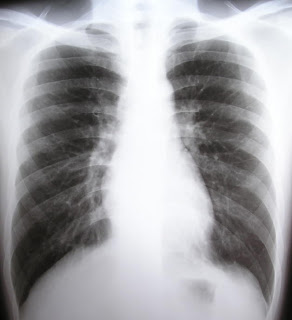

Well, obviously, you say. If we didn’t breathe, we’d be dead. True, but I speak of the quality of breathing. Most people breathe from the upper chest. To go deeper and lower, from the diaphragm, slowing down the rate and focusing on the exhale has so many benefits that can literally change the frequency of the world.